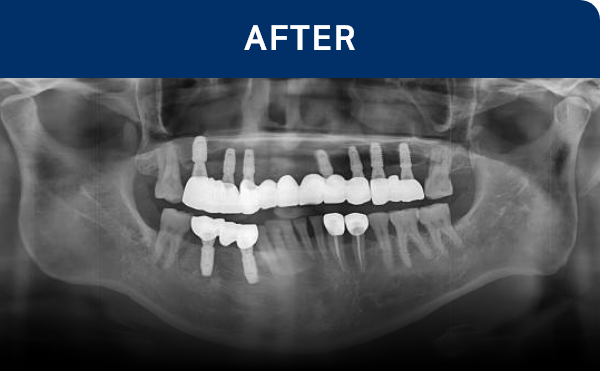

种植牙是在精准诊断与治疗计划的基础上,

通过多个步骤进行的治疗方式

会根据患者的口腔状况, 分阶段安全推进

种植牙是一项高难度治疗,

需依赖精密检查与充分的术前计划

因此, 选择具备丰富经验与专业技术的

医疗团队尤为重要